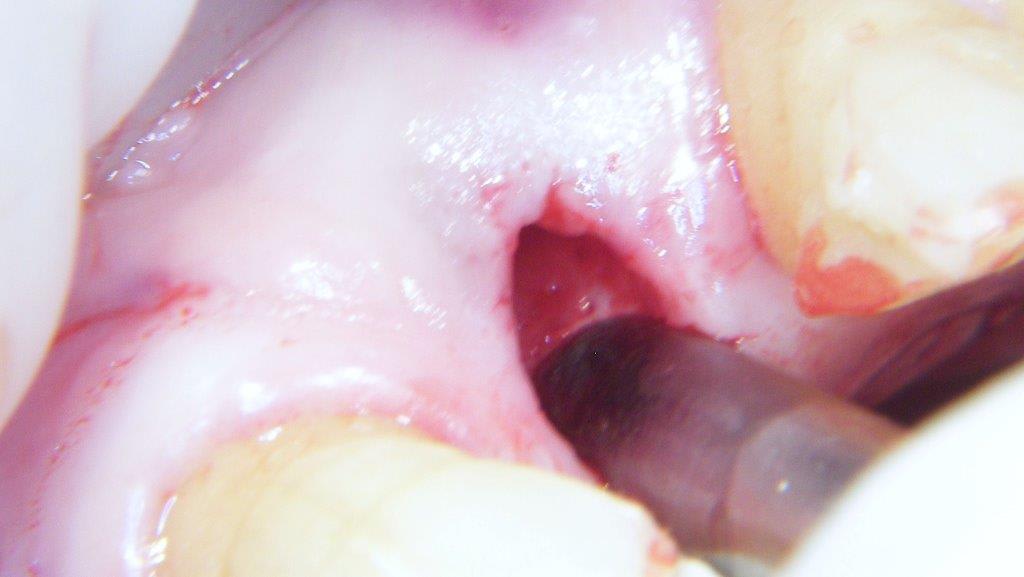

pour ceux que ça intéressent, une petite utilisation d'expansion de la paroi palatine, sur une avulsion d’incisive(racine fendue). toutes mes excuses pour la mauvaise qualité des photos.